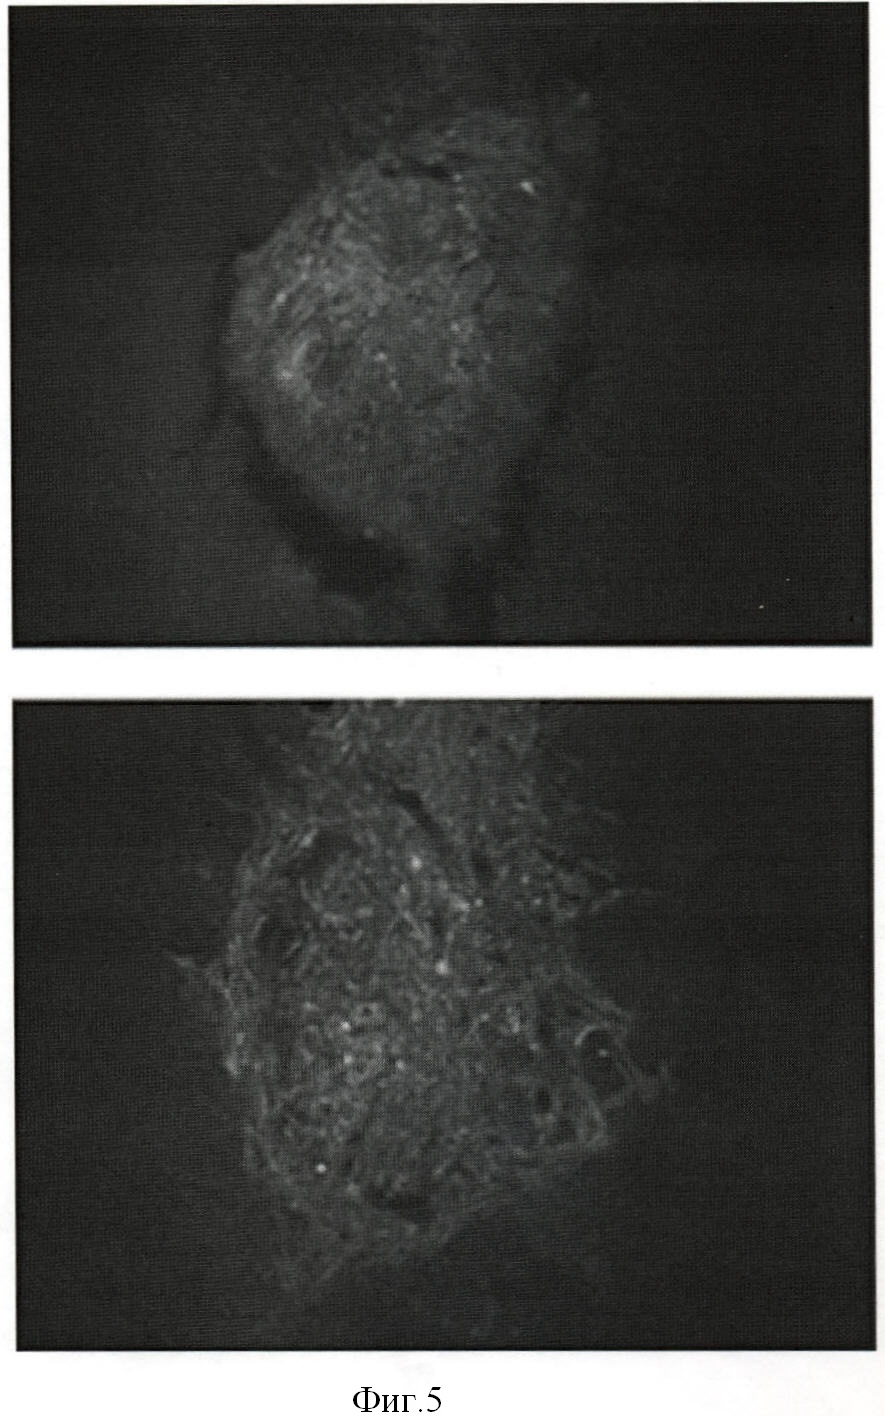

Фиг.5. Распределение GFP-меченных клеток в стриатуме мозга через 10 дней после трансплантации. Верхняя панель – индуцированная (BDNF) субпопуляция СКЖТ, не экспрессирующих TrkB; нижняя панель – индуцированная (BDNF) субпопуляция СКЖТ, экспрессирующих TrkB.

Через 10 дней мышей перфузировали 4% формалином, извлекали головной мозг и фиксировали 3-5 часов в 4% формалине, затем инкубировали 10-16 часов в 30% сахарозе и замораживали. Далее делали срезы толщиной 20 мкм на криостате (НМ 505 Е, Microm, Германия). Готовые препараты хранили при +4°С в темноте. Полученные препараты (Фиг.5) анализировали при помощи флуоресцентного микроскопа Axiovert 200М (Zeiss). Документирование изображений производили с помощью цифровой видеокамеры Axiocam HRC (Zeiss, Германия) и обработки изображения в программе Axiovision 3.1. Индуцированные in vitro СКЖТ клетки, не экспрессирующие TrkB, за указанное время не обнаруживали вступления в контакт с тканью реципиента и оставались в области трека. За тот же период времени клетки, экспрессирующие TrkB, будучи индуцированы в направлении нейральной дифференцировки, демонстрировали выраженную миграцию в паренхиму мозга (Фиг.5).